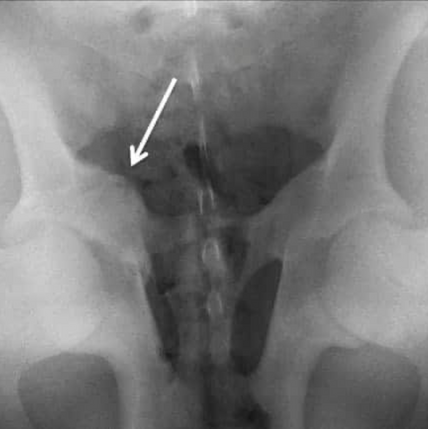

Hairline fractures (also known as stress fractures) are among the most challending to identify due to imaging limitations. MRI and/or bone scintigraphy are the preferred diagnostic modality for humans [2] because these types of fractures do not always show up on X-Rays or ultrasound, which begs the question, what about our horses?

Ultrasound or X-Ray may be the next best diagnostic option, however, are not always conclusive depending on size and fracture location.

Pelvic X-Ray

Pelvic Fracture